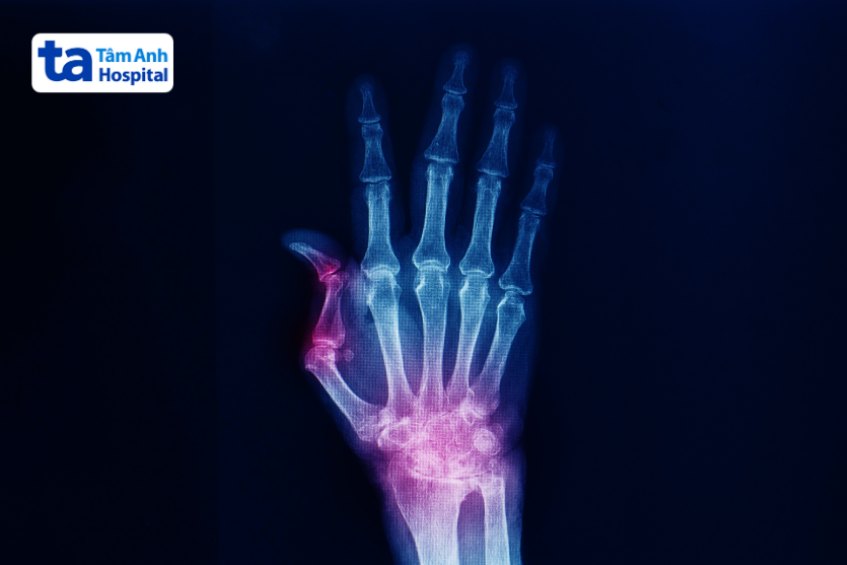

Chấn thương ngón tay bao gồm chấn thương khớp ngón tay và chấn thương phần mềm ngón tay, là tình trạng một hoặc nhiều ngón tay bị tổn thương bởi tác động của ngoại lực do va đập, té ngã hoặc tai nạn, không phải do bệnh lý. Chấn thương ngón tay gây ảnh hưởng đáng kể đến cuộc sống hàng ngày và sức khỏe tổng thể của người bệnh.

Thăm khám cận lâm sàng bao gồm nhiều kỹ thuật như siêu âm, chụp X-quang, chụp cắt lớp (CT), chụp cộng hưởng từ (MRI)… được bác sĩ cân nhắc chỉ định thực hiện nhằm hỗ trợ quá trình chẩn đoán và điều trị bệnh chuẩn xác. (3)

Chẩn đoán chấn thương ngón tay nhằm mục đích xác định nguyên nhân. Dựa trên mức độ chấn thương, bác sĩ có thể chỉ định phương pháp điều trị thích hợp, hiệu quả. Quá trình chẩn đoán bao gồm thăm khám lâm sàng và cận lâm sàng.